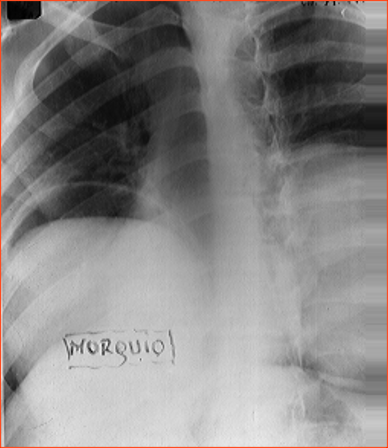

Rx toracică, incidență P-A

DESCRIERE:

DX: emfizem pulmonar

DD: